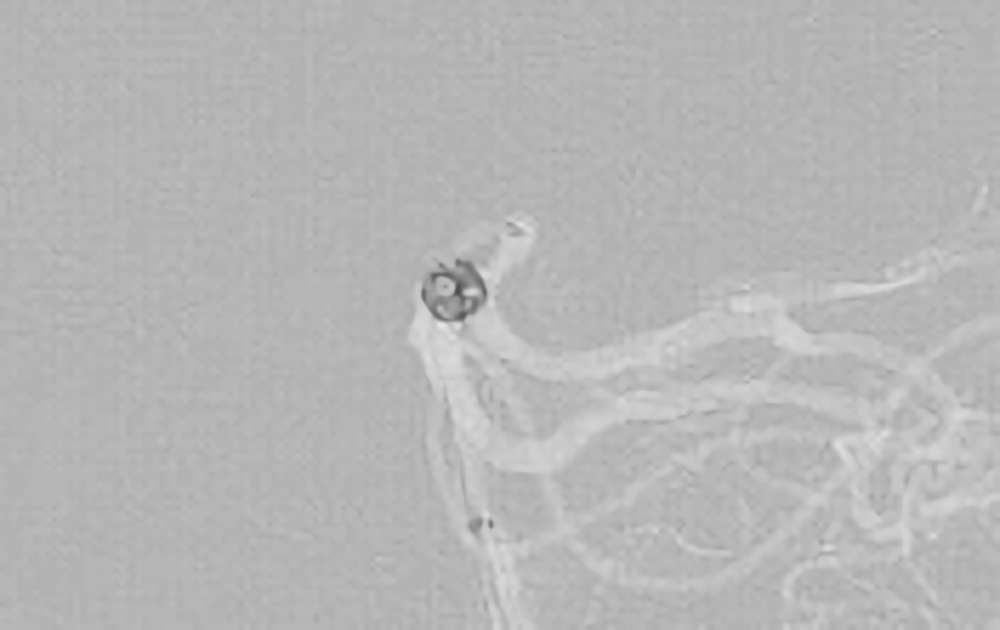

No.1631 手術前